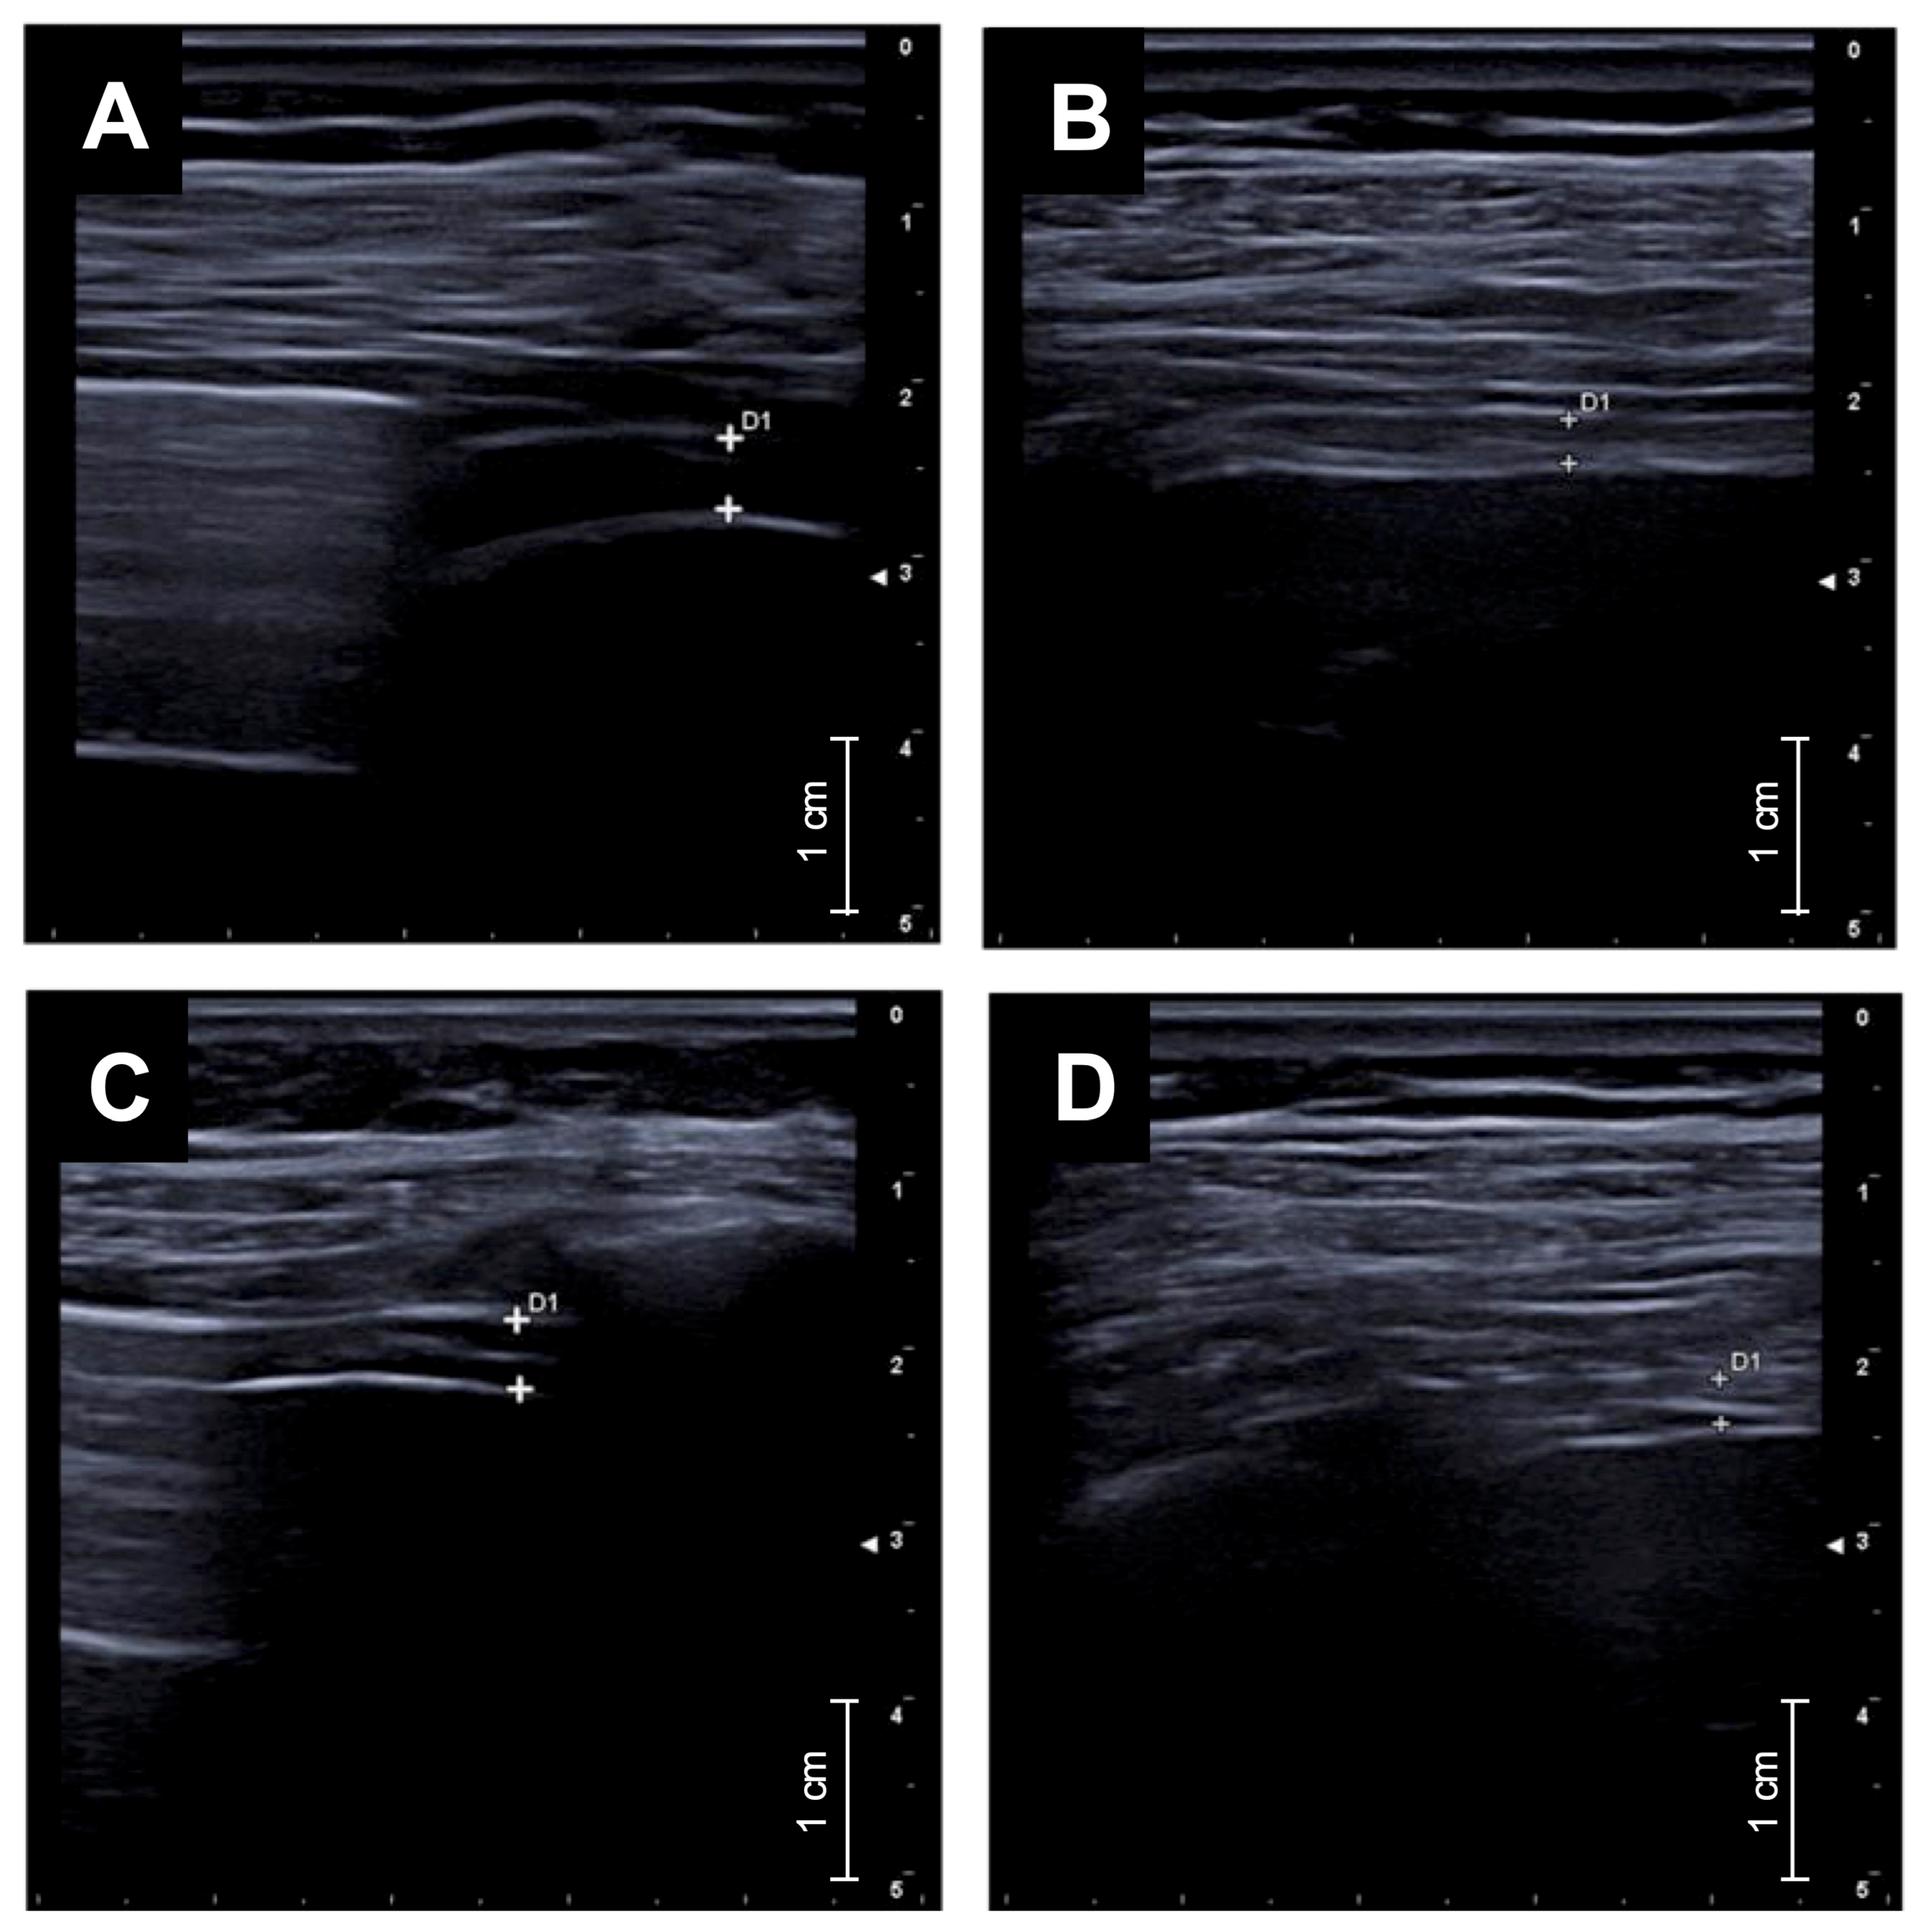

- Diaphragmatic ultrasound showed a marked reduction in diaphragmatic thickening fraction, indicating decreased respiratory workload.

- Diaphragmatic ultrasound could represent a novel, non-invasive biomarker to monitor treatment response in uncontrolled asthma.

2.2. Diaphragmatic Ultrasound Protocol

- Maiorano, A.; Lupia, C.; Montenegro, N.; Neri, G.; Bruni, A.; Garofalo, E.; Longhini, F.; Crimi, C.; Maglio, A.; Vatrella, A.; et al. Effects of inhaled beclomethasone dipropionate/formoterol fumarate/glycopyrronium on diaphragmatic workload and lung function in uncontrolled asthma: A case report. Front. Med. 2024, 11, 1357362. [Google Scholar] [CrossRef] [PubMed]